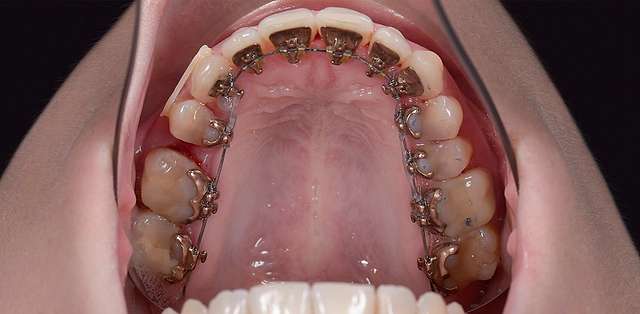

One of the advantages of lingual braces, outside of the obvious one (the fact that it's socially invisible) is that it will preserve intact the buccal surface of teeth. It has a somewhat more complex and difficult biomechanic to manage, but it has its niche for patients who want their teeth straightened but don't want braces to be visible. Lingual braces are usually made from gold, have a high degree of biocompatibility and prevent secondary caries.